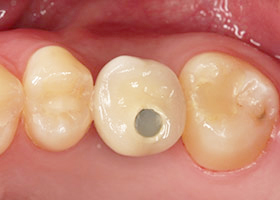

水雷射治療可以縮短傷口癒合與手術過程時間,大幅度減少手術中所產生流血量與疼痛感,十分害怕手術疼痛而拒絕看診的患者來說,水雷射治療提供您安全低疼痛又可以免除恐懼的植牙方式。